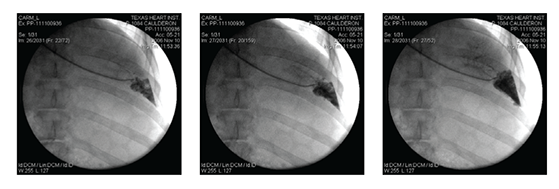

We established a veno-venous (V-V) steady-state, closed loop circuit confirmed by fluoroscopy (Figure 1); the drug regimen was then administered to the site. The schedule for sample collection was designed to estimate and determine, by trial-and-error, the time of occurrence and the duration of drug exposure.

Figure 1 A catheter positioned in the hepatic vein; time sequence of the radio-opaque dye injected into the targeted area.